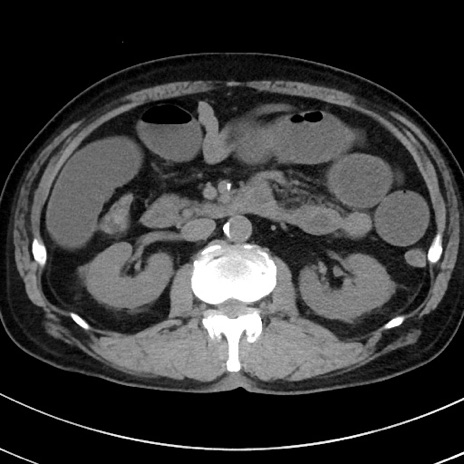

冠状断像

症例38(横断像)

【症例】70歳代 男性

【主訴】腹痛・嘔吐

【現病歴】昨晩より、嘔吐・腹痛あり。今朝になっても嘔吐あり。来院。

【既往歴】心臓バイパス手術、開腹胆摘、腸閉塞

【身体所見】BP 107/71mmHg、HR 116/min、腹部:平坦、軟、下腹部に軽度圧痛あり。反跳痛なし。

【データ】WBC 15100、CRP 0.32